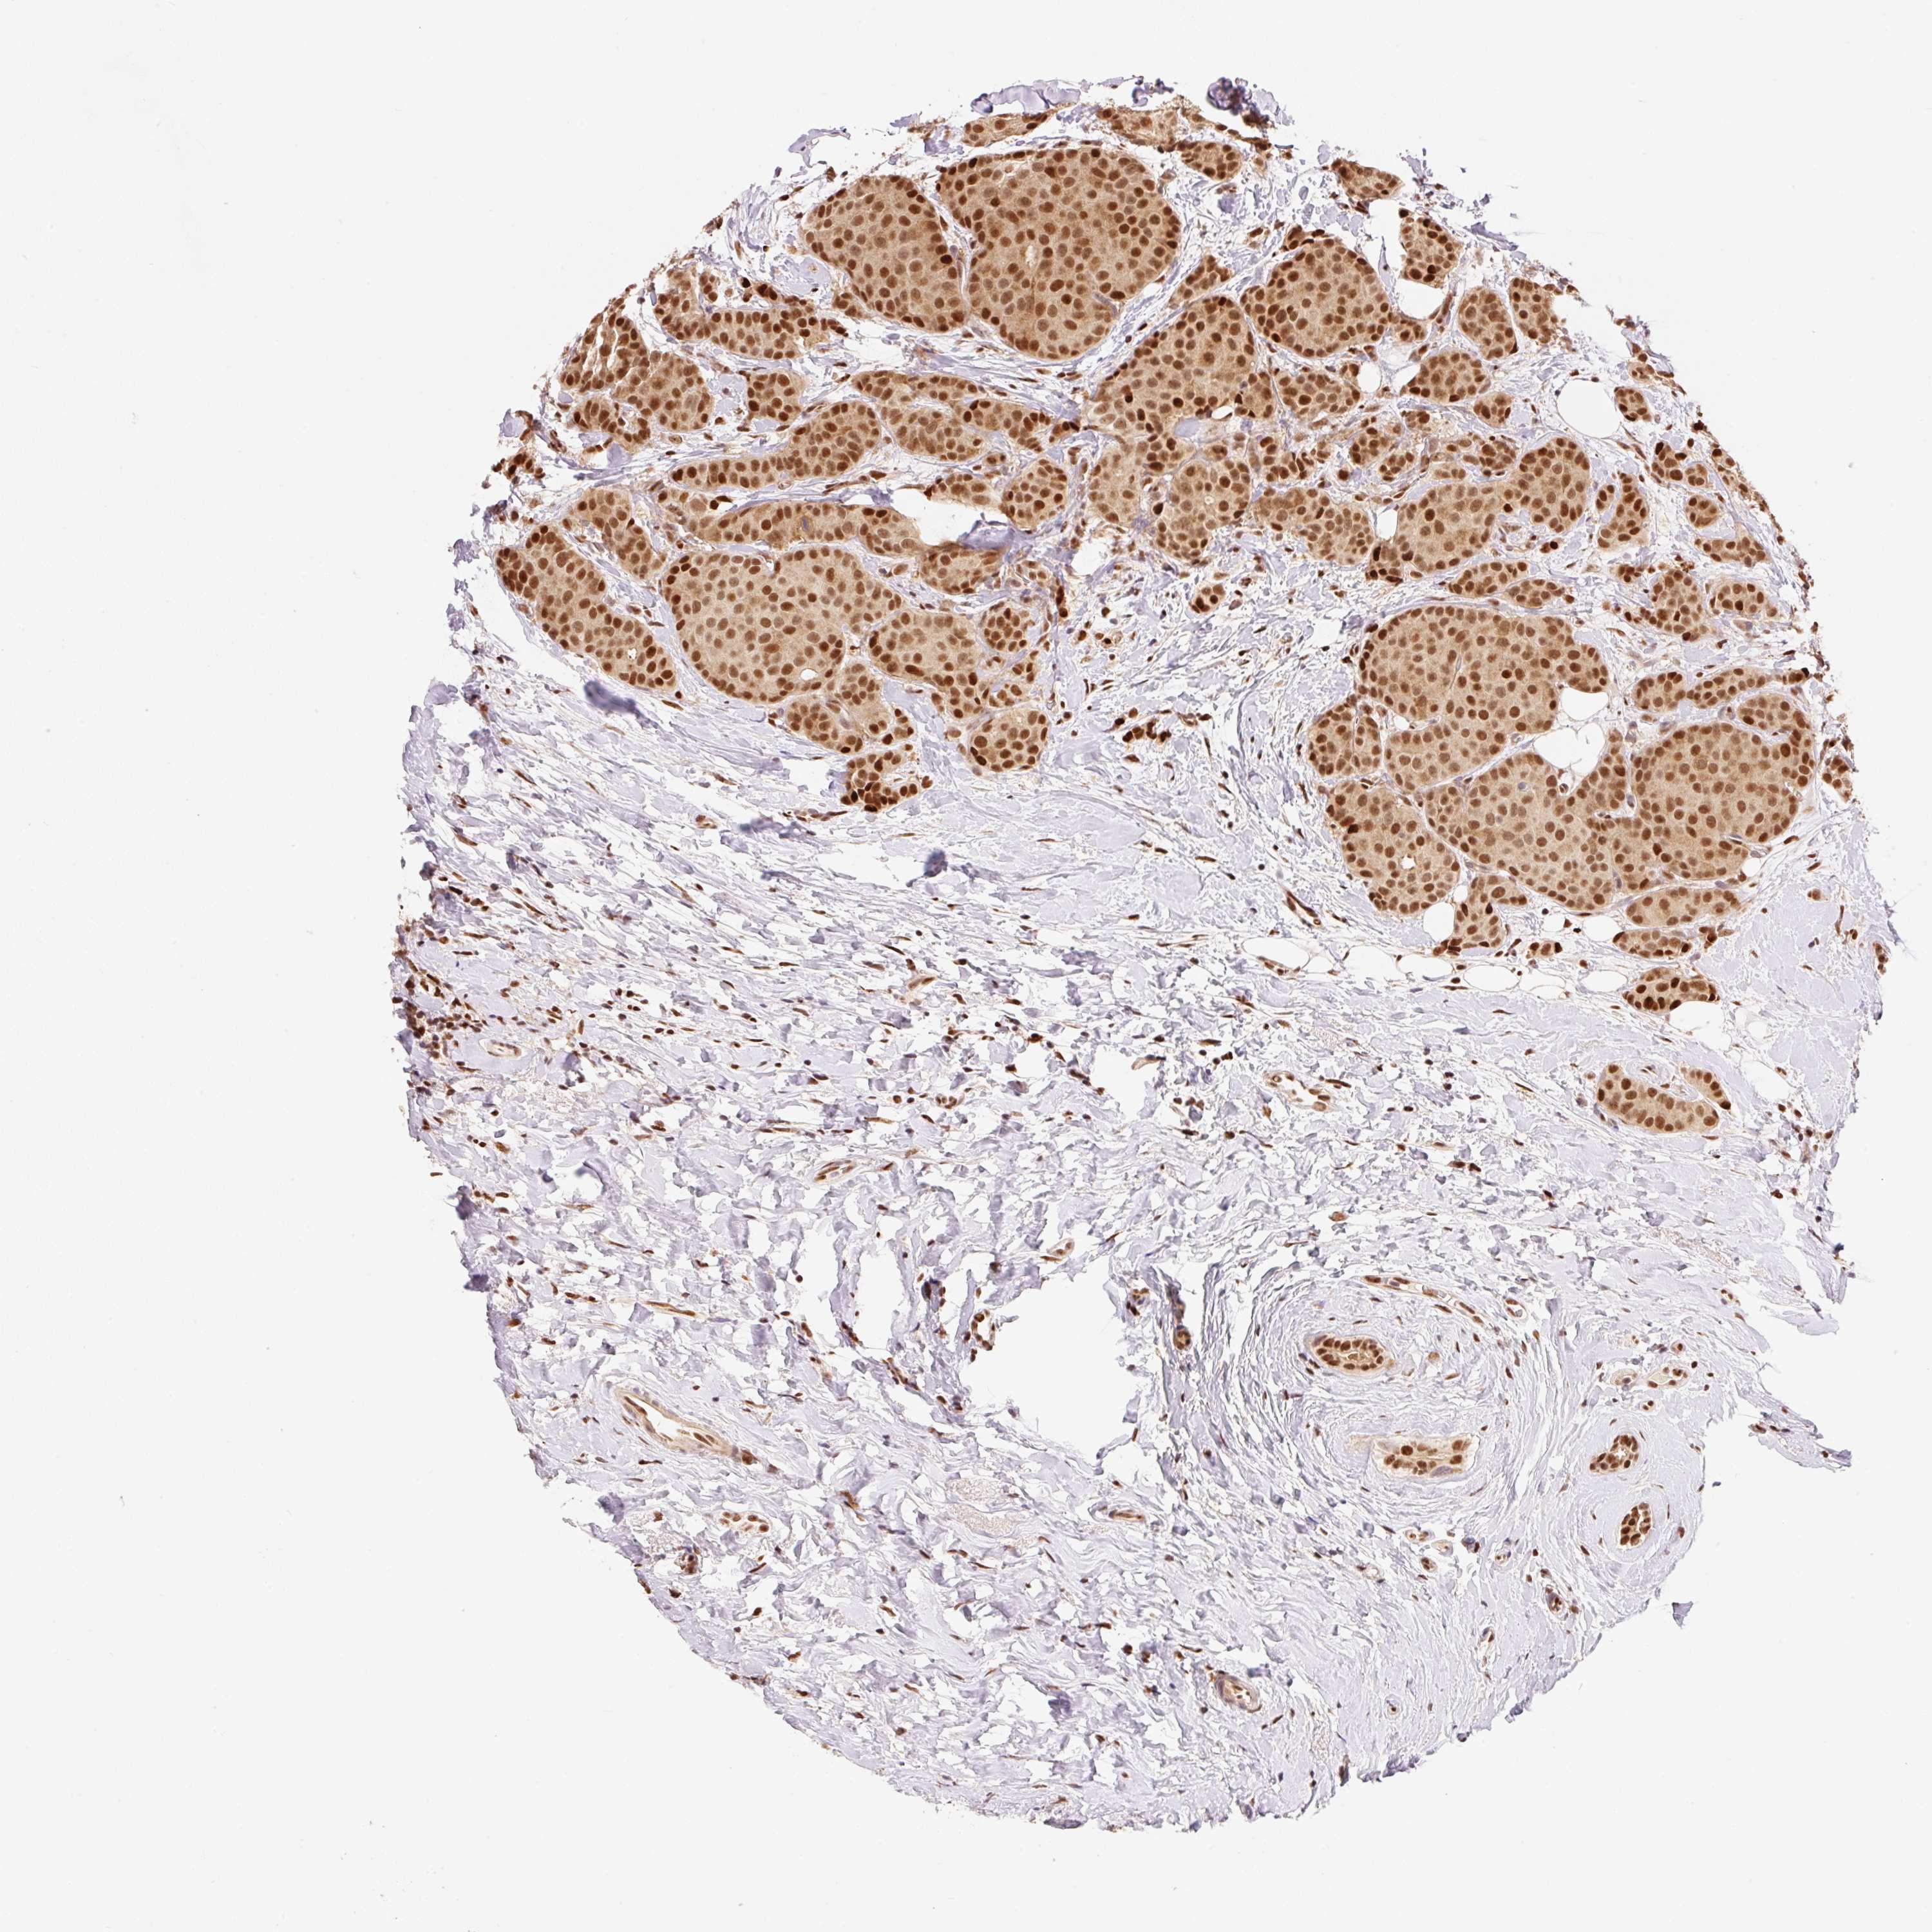

CANCER BREAST CANCER Show tissue menu

BRCA TCGA BRCA VALIDATION PROTEIN EXPRESSION

Breast cancer

Human cancer